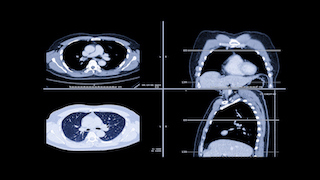

CT scan images of lungs

CT screening can see smaller objects and catch lung cancer at stage 2 or earlier, which can make a big difference in terms of therapies and treatment options.